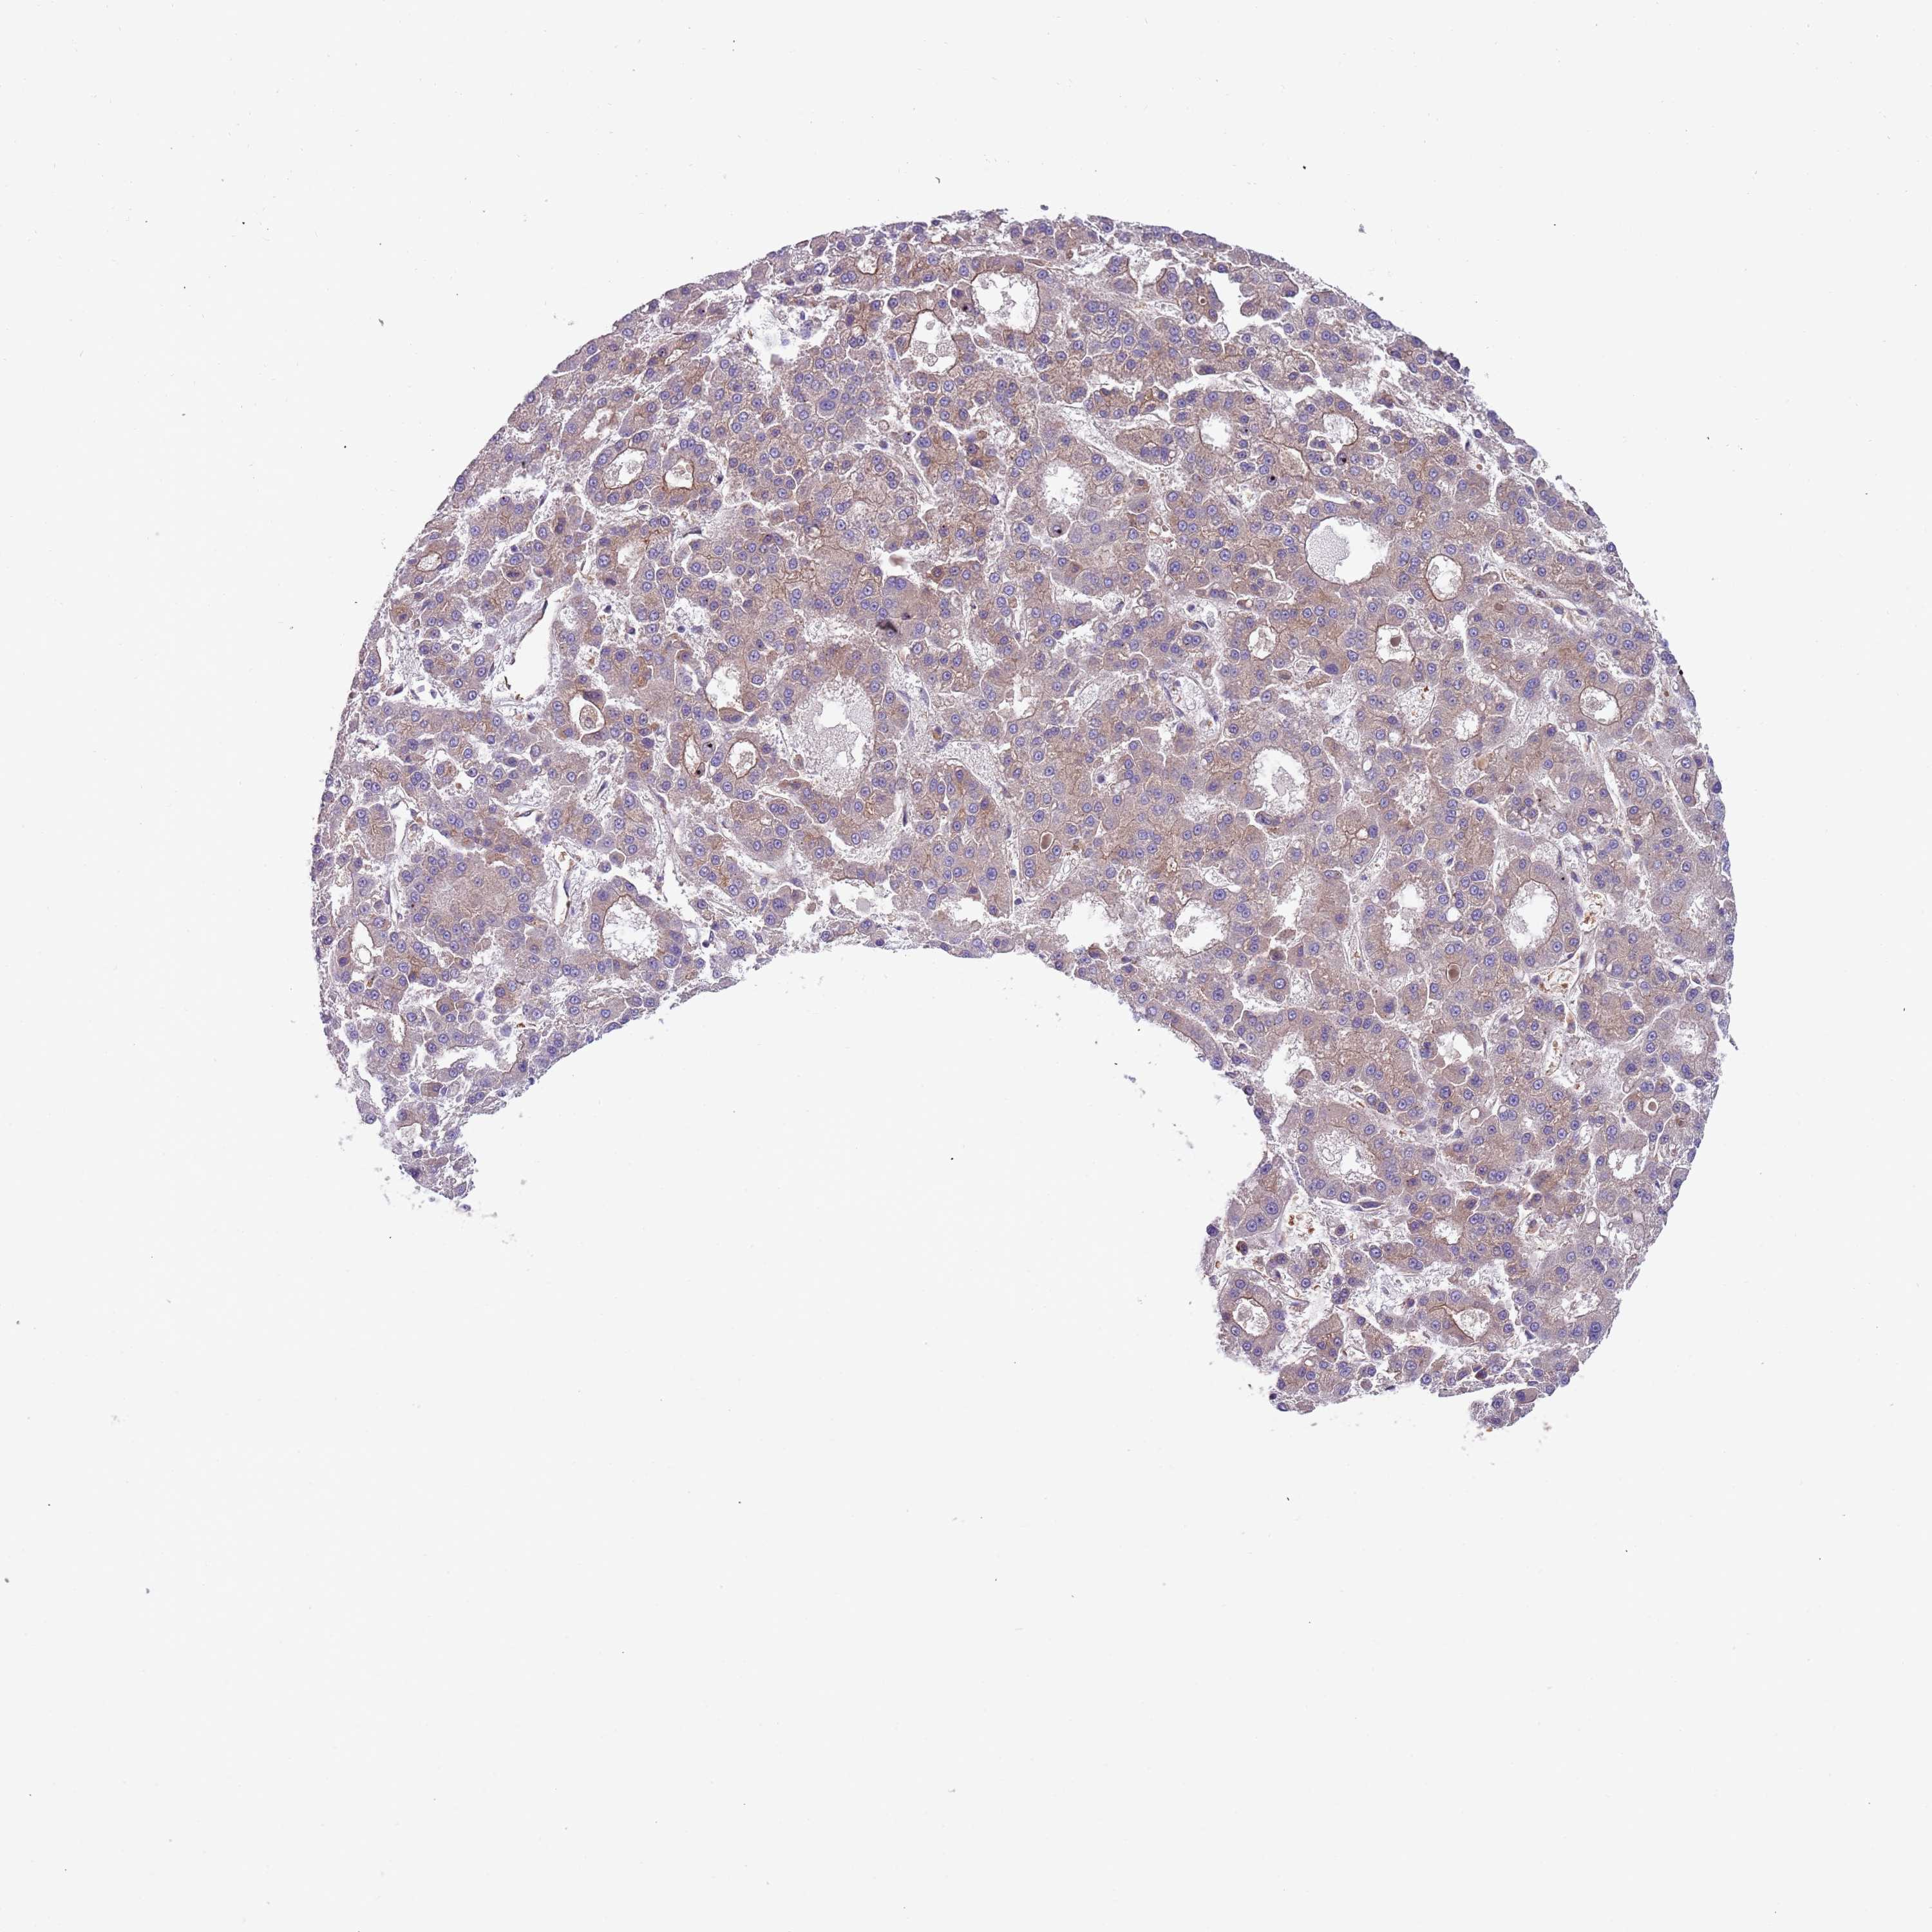

LIVER CANCER - Protein expressioni

A mouse-over function shows sample information and annotation data. Click on an image to view it in a full screen mode. Samples can be filtered based on level of antibody staining by selecting one or several of the following categories: high, medium, low and not detected. The assay and annotation is described here.

Note that samples used for immunohistochemistry by the Human Protein Atlas do not correspond to samples in the TCGA dataset.

Antibody stainingi

Antibody staining in the annotated cell types in the current human tissue is reported as not detected, low, medium, or high, based on conventional immunohistochemistry profiling in selected tissues. This score is based on the combination of the staining intensity and fraction of stained cells.

Each image is clickable and will lead to virtual microscopy that enables deeper exploration of all samples and also displays staining intensity scores, fraction scores and subcellular localization as well as patient and tissue information for each sample.

Antibody HPA040401

Antibody HPA043921

Staining

High

Medium

Low

Not detected

Intensity

Strong

Moderate

Weak

Negative

Quantity

>75%

75%-25%

<25%

None

Location

Nuclear

Cytoplasmic/membranous

Cytoplasmic/membranous,nuclear

Cholangiocarcinoma

Carcinoma, Hepatocellular, NOS